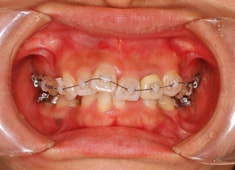

治療開始時

治療開始から1年8ヶ月後